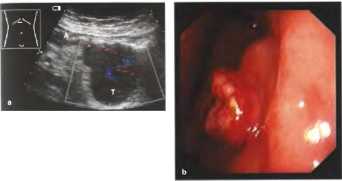

В качестве примера визуализации патологии с помощью сонографии можно привести гастросонорграммы опухолей антрального отдела желудка в сравнении с нормальной ЭХО-картиной органа.

Рис. 22. Осмотр антрального отдела желудка на поперечном сечении: а, b Плоская асимметричная полиповидная опухоль (Т), глубоко инвазирующая стенку желудка и прорастающая ее: стромальная опухоль ЖКТ (GIST), в данном случае злокачественная и уже с метастазами. А - антральная часть, b Эндоскопическая картина. Результаты биопсий были отрицательными.

Рис. 20. b а Карцинома желудка: опухоль (Т) антрального отдела со сложной эхоструктурой. b Полиповидная опухоль (Т), гистологически идентичная с карциноидом.